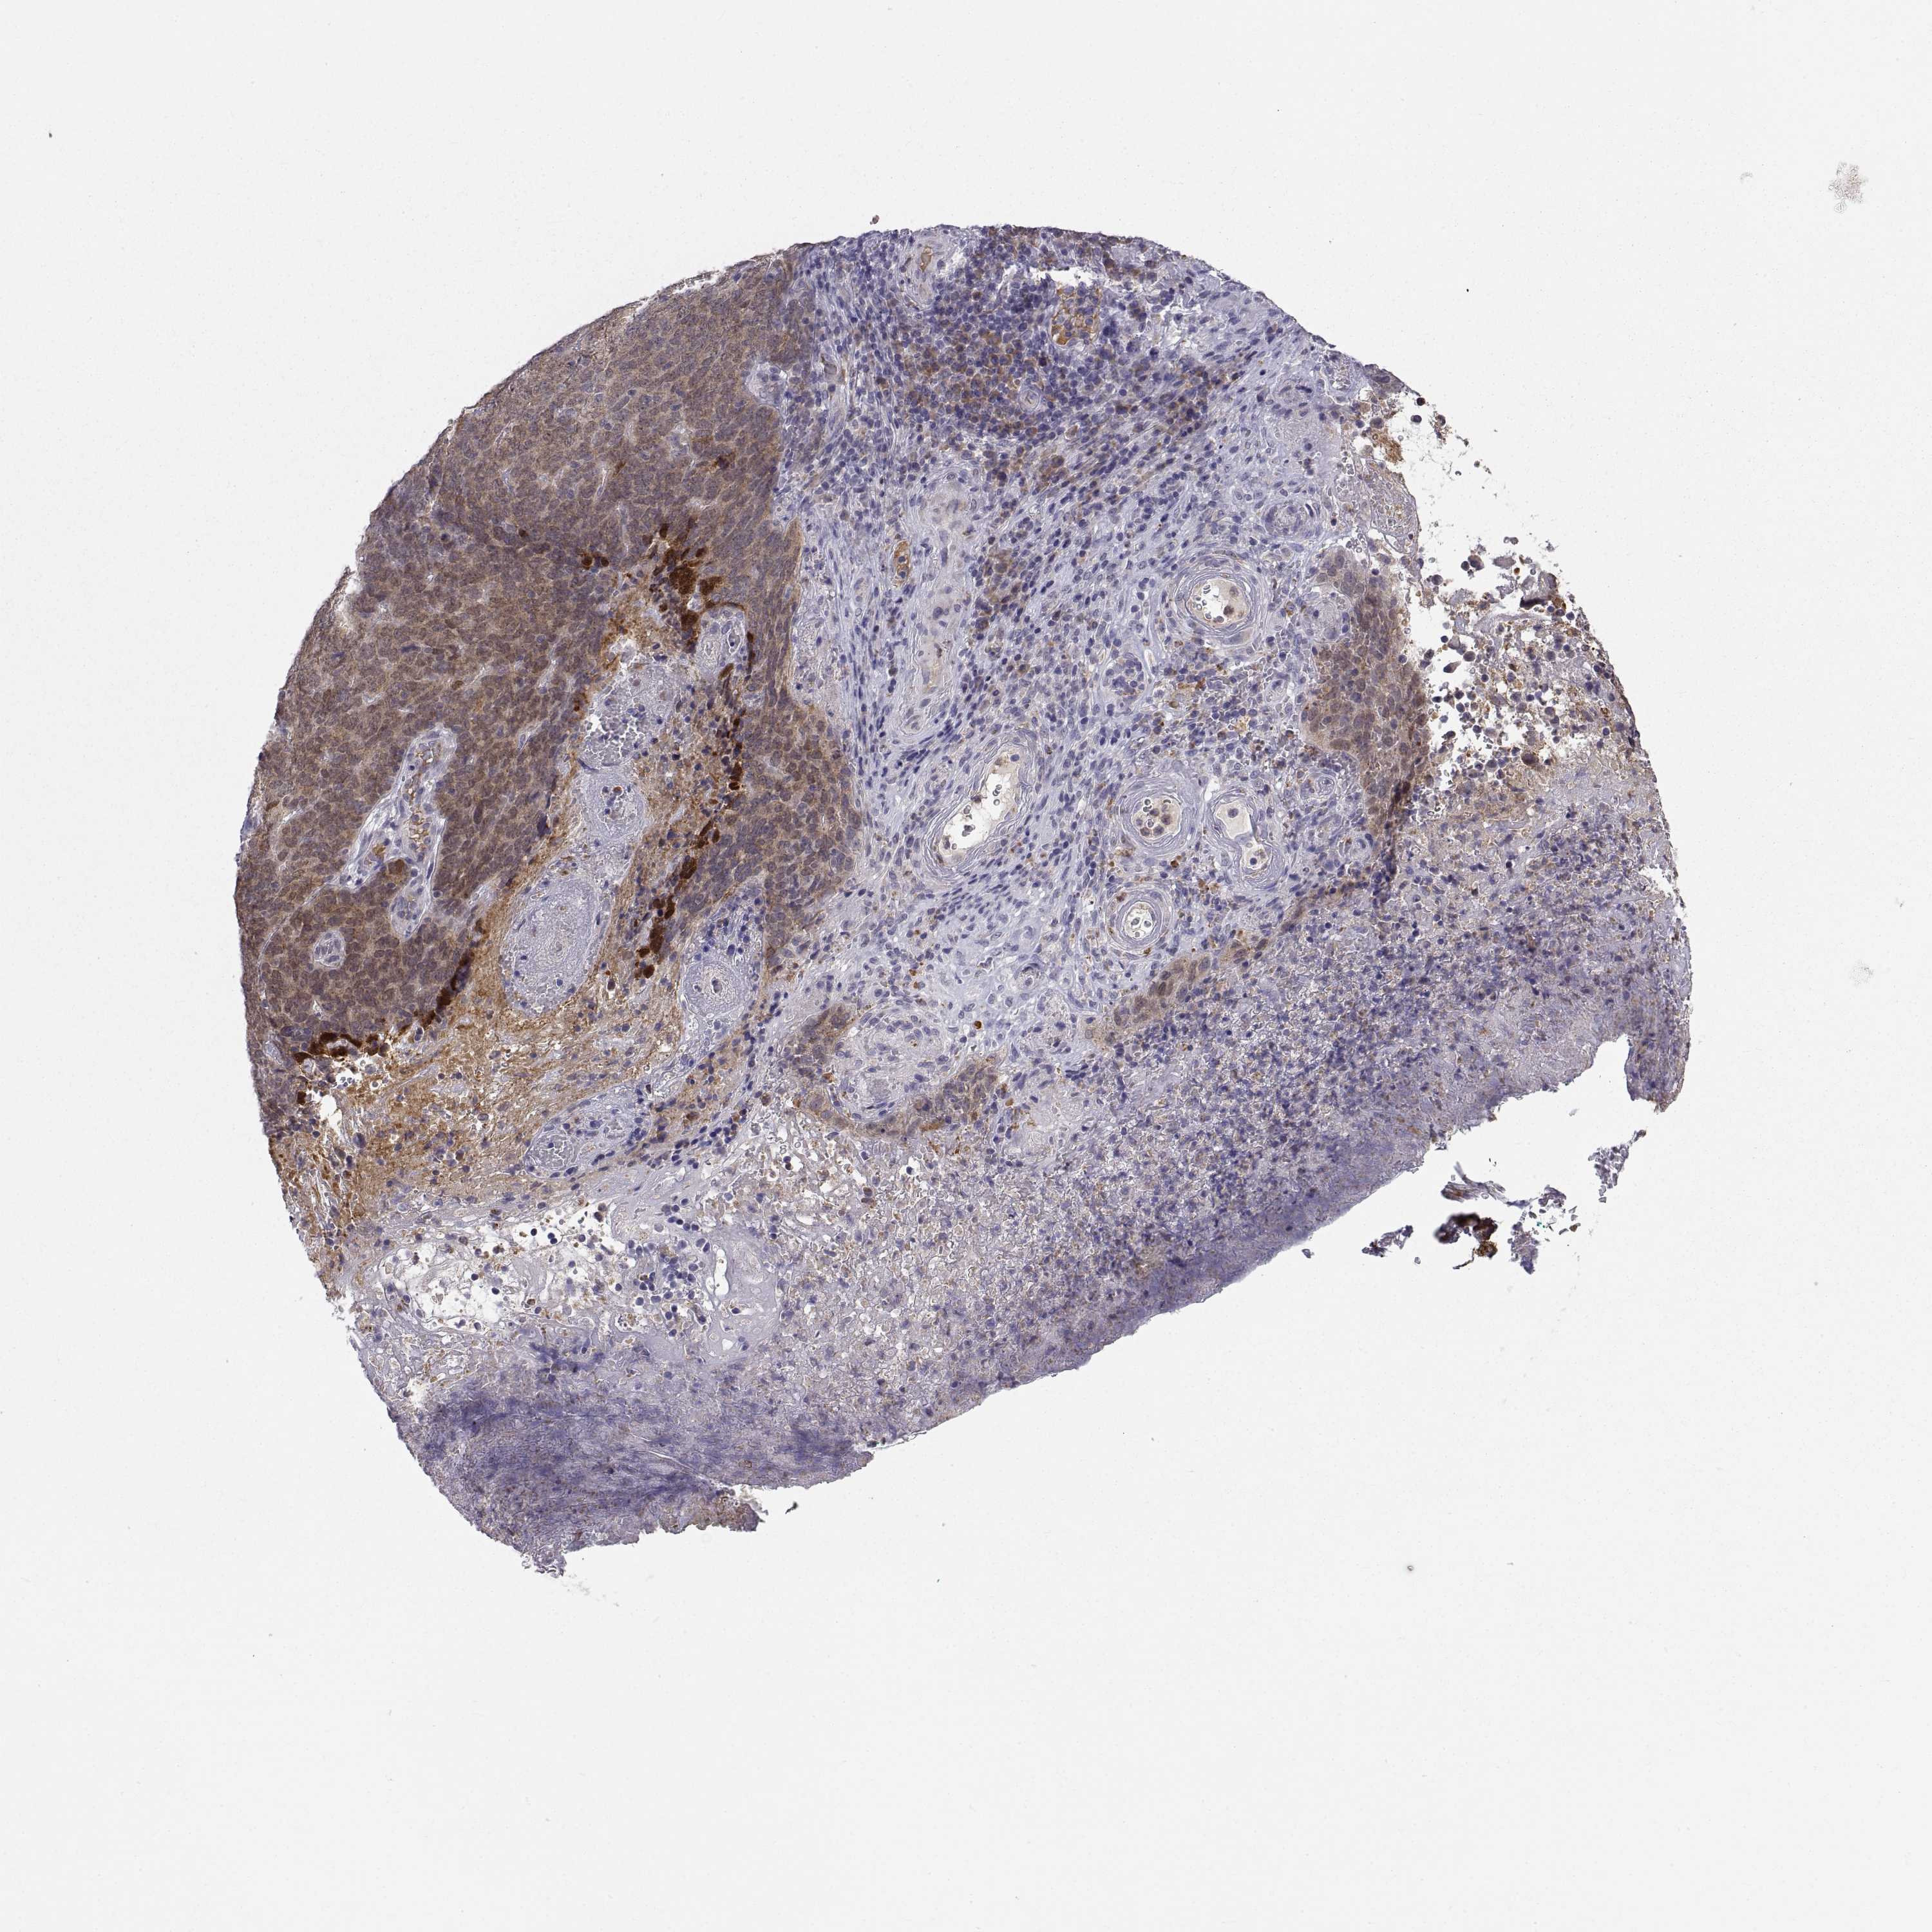

SKIN CANCER - Protein expressioni

A mouse-over function shows sample information and annotation data. Click on an image to view it in a full screen mode. Samples can be filtered based on level of antibody staining by selecting one or several of the following categories: high, medium, low and not detected. The assay and annotation is described here.

Each image is clickable and will lead to virtual microscopy that enables deeper exploration of all samples and also displays staining intensity scores, fraction scores and subcellular localization as well as patient and tissue information for each sample.

Antibody HPA027221

Basal cell carcinoma

Squamous cell carcinoma, NOS